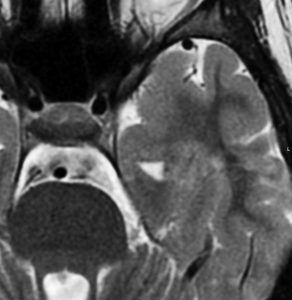

左は8歳時のMRIで,異常所見がありませんでした。左側頭葉に発作時の異常脳波所見が認められ,側頭葉てんかんの診断でカルバマゼピンの投与が開始されました。9歳時に精神症状を呈する発作となりレベチラセタムとゾニザミドが加えられました。右側のMRIは9歳時のものですが異常所見はありませんでした。前後にさまざまな画像が撮影されていましたが脳腫瘍の所見はありませんでした。

11歳時のMRIで側頭葉下面に異常所見が出現しました。

12歳時,私のところへ来た時のガドリニウム増強像です。開頭手術で扁桃体を含めて全摘出してから発作は止まり,術後3年で抗てんかん薬は中断できています。